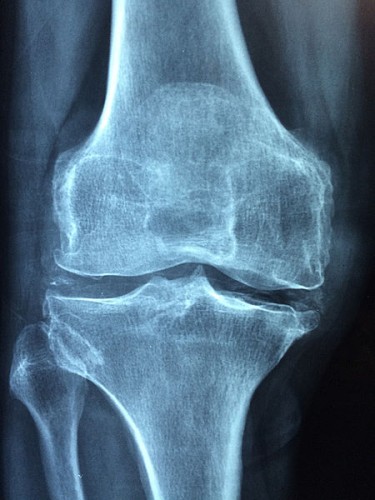

Radiografía de rodilla. (Foto: UN)

Las personas con osteoartritis en fase inicial es una población objetivo ideal para detectar características relevantes de biomarcadores de etapas más tempranas de la enfermedad.Por ello, se ha realizado un seguimiento durante noventa y seis meses de cuatro mil setecientos noventa y seis individuos. En concreto, se han procesado muestras de personas que no tenían significativamente afectada la rodilla por la osteoartritis, pero con características específicas que les predisponían a desarrollar osteoartritis en la rodilla. Además, se incluyeron muestras de un grupo de control, cuyos participantes no tenían síntomas de osteoartritis en la rodilla ni los factores de riesgo. El objetivo último era detectar anticuerpos en el suero de estas personas que pudieran ser útiles para predecir la incidencia de la osteoartritis en rodilla. Este estudio ha permitido detectar un panel específico de autoanticuerpos en individuos que comienzan a desarrollar osteoartritis en rodilla (ya detectable a través de radiografía) durante un período de seguimiento de noventa y seis meses, en comparación con aquellos que se mantuvieron sanos.